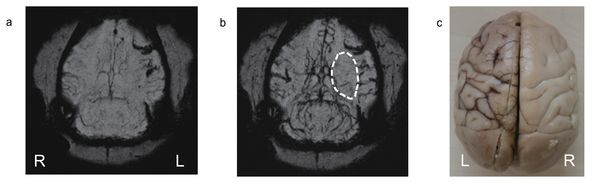

Finally, after the successful use of PEG-IONCs in static MRA, the scientists conducted a more challenging dynamic imaging to see vascular flow patterns of cerebral ischemia (the cause of stroke) in dogs and monkeys. Cerebral ischemia is a disorder caused by insufficient blood flow to the brain and its early detection with MRI contrast agents is vital for survival of patients. In the experiment, images were taken at several time points, every 1.5 seconds after injection of the contrast agent to see the blood perfusion patterns in the brain. An occlusion in the middle cerebral artery was detected.